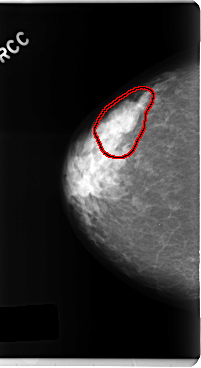

FILE: C_0247_1.RIGHT_MLO.OVERLAY

TOTAL_ABNORMALITIES 1

ABNORMALITY 1

LESION_TYPE MASS SHAPE LOBULATED MARGINS CIRCUMSCRIBED

ASSESSMENT 3

SUBTLETY 4

PATHOLOGY BENIGN

TOTAL_OUTLINES 1

BOUNDARY